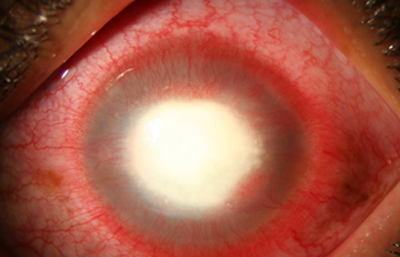

Superficie corneal irregular y grisácea, (Fig. 1, 2) con opácidades granulares en parche y formación de líneas epiteliales elevadas de aspecto granular (Fig. 3), que pueden arborizar dando imágenes de pseudodendritas. Opacidades superficiales satélites. (Figura 4) Inyección ciliar. Ulceración epitelial variante. (Figura 5).

Fig. 2 Síntomas de 25 días evolución